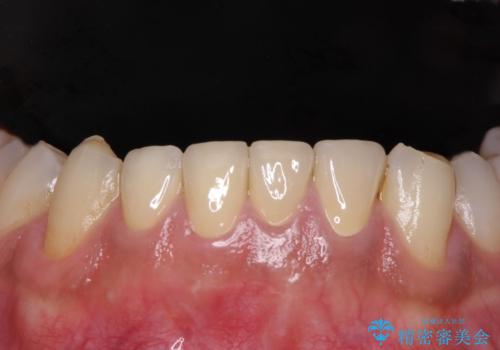

- 奥歯の大きな虫歯により歯が失われてしまい、大きく口を開けると歯がないことが周りの人に見えてしまうことを気にされていた患者様です。

前方の歯については学生時代の矯正治療の際、装置周りに多数の虫歯を作ってしまっていました。

右上の犬歯は歯肉退縮が著しく、歯肉移植による根面被覆を提案しましたが、しばらくは様子を見たいとのことでした。

クラウンの縁の位置は将来の根面被覆に対応できるような位置に設定することにしました。